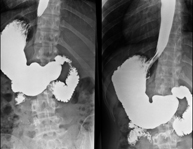

- TEGD (Tránsito Esófago – Gastro – Duodenal)

Prueba diagnóstica que consiste en obtener imágenes radiológicas en movimiento del esófago, el estómago y el duodeno mediante el empleo de rayos X (fluoroscopia) y de un contraste opaco baritado que se administra por vía oral.

- Tránsito intestinal

Prueba diagnóstica que consiste en obtener imágenes radiológicas en movimiento del esófago, el estómago, el duodeno y el intestino delgado mediante el empleo de rayos X (fluoroscopia) y de un contraste opaco baritado que se administra por vía oral.